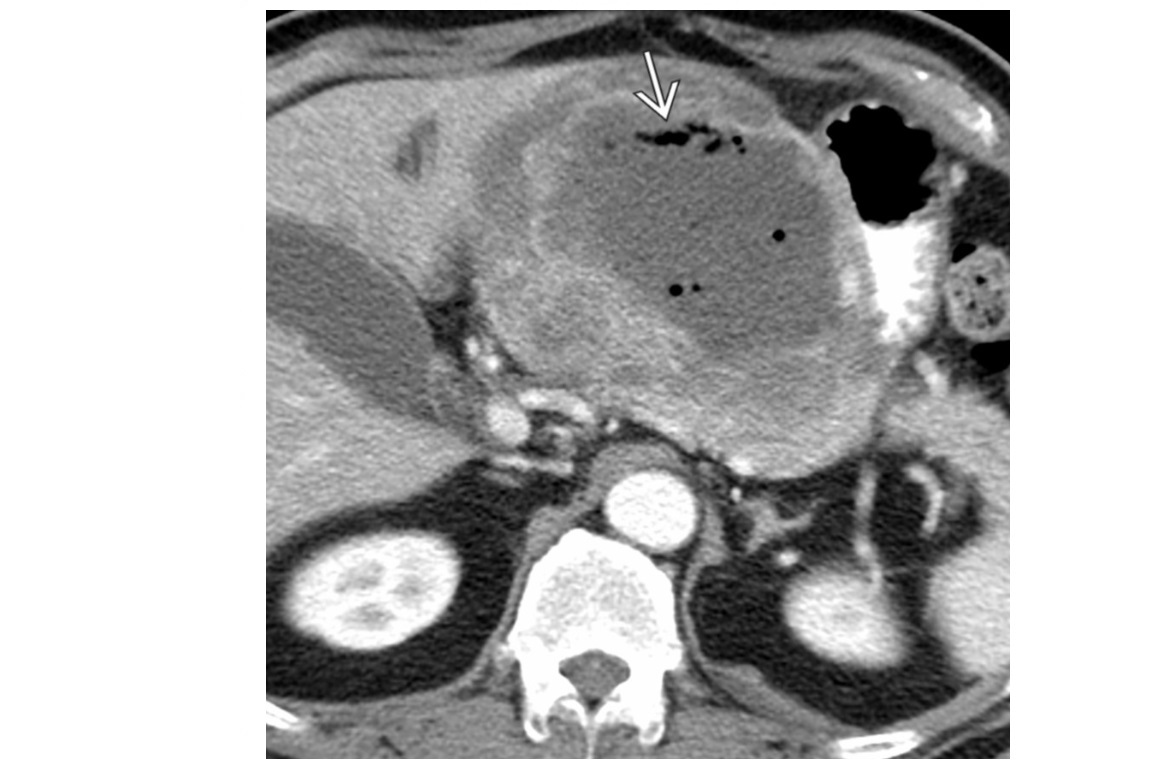

GIST

Well-circumscribed.

**Heterogenous, central necrosis is key **

Hypervascular

submucosal mass extending exophytically from GI tract

Stomach (60%) , dudoenum (30%) and oesophagus (10%)

Remember

- assocaited NF-1

- Carneys triad

- Pulmonary condromas, Exrtra-adrenal paragangliomas, GIST